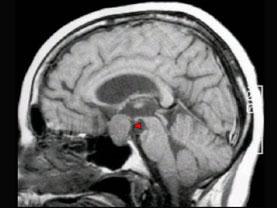

问题 男,37岁,视力模糊,部分视野缺失,伴有头痛、恶心数月,MRI检查如图,最可能的诊断为 ( )

选项 A、垂体瘤 B、表皮样囊肿 C、脑膜瘤 D、蛛网膜囊肿 E、颅咽管瘤

答案 A